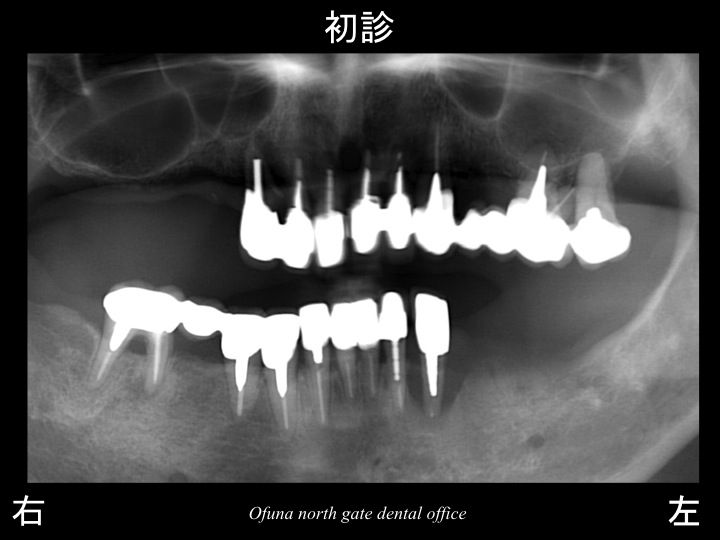

『232回目のインプラント症例』です。

本日ご紹介する症例(再アップケース)は、治療することが多く、

本当に大変なケースでした。

なにが大変であったかと言いますと

単に欠損部位が多いというだけでなく、

現在残っている歯の状態が悪かったのです。

初診時歯は16本残っていましたが、(全て残っている方は28歯です)

全て神経がない歯であり、

大きく虫歯 になっていたり、

歯根破折 していたり

噛み合わせが大きくズレていたり、

欠損部も骨吸収が非常に大きかったり、

全体的に問題が多くある患者様でした。

以下は初診時です。

先にも説明しましたように さまざまな問題ありました。

患者様の主訴としては、

上顎右側の歯に穴があいており、物が詰まり、腫れている状態でした。

下顎の左側の奥歯も歯肉が腫れており、歯自体がグラグラな状態でした。